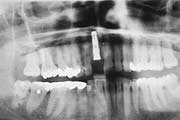

Um eine möglichst präzise Diagnostik und Planung zu ermöglichen, arbeiten wir mit modernsten, computerunterstützten Navigationssystemen auf der Basis von 3D Tomographiescans des Implantationsgebietes. Damit werden häufig knochenaufbauende Vorbehandlungen überflüssig und das Plazieren der Implantate schonender und risikoärmer.

Wann machen Implantate Sinn?

Einzelzahnersatz

Gesunde Nachbarzähne müssen nicht beschliffen werden. Eine

unauffällige und natürliche Lösung. Anspruchsvoll in

der Ästhetik und langfristig im Nutzen.